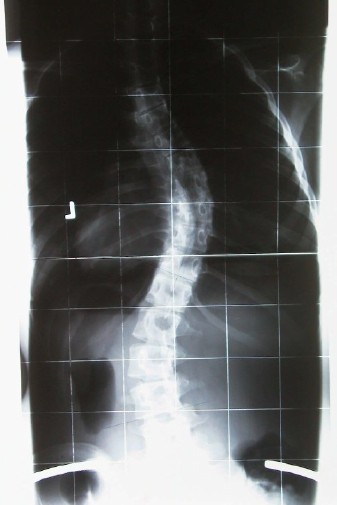

Um mal zu zeigen wie ein hohe Primärkorrektur wirklich aussieht:

- 50° Cobb.o.K.jpg (29.18 KiB) 24077 mal betrachtet

- Im Korsett.jpg (28.78 KiB) 24078 mal betrachtet